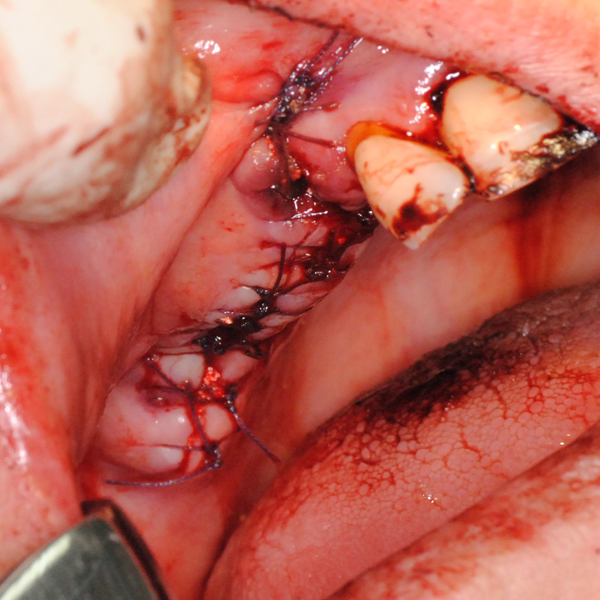

Схема на открития синуслифтинг

Видеоклип за открит синуслифтинг Пластинка Сasios